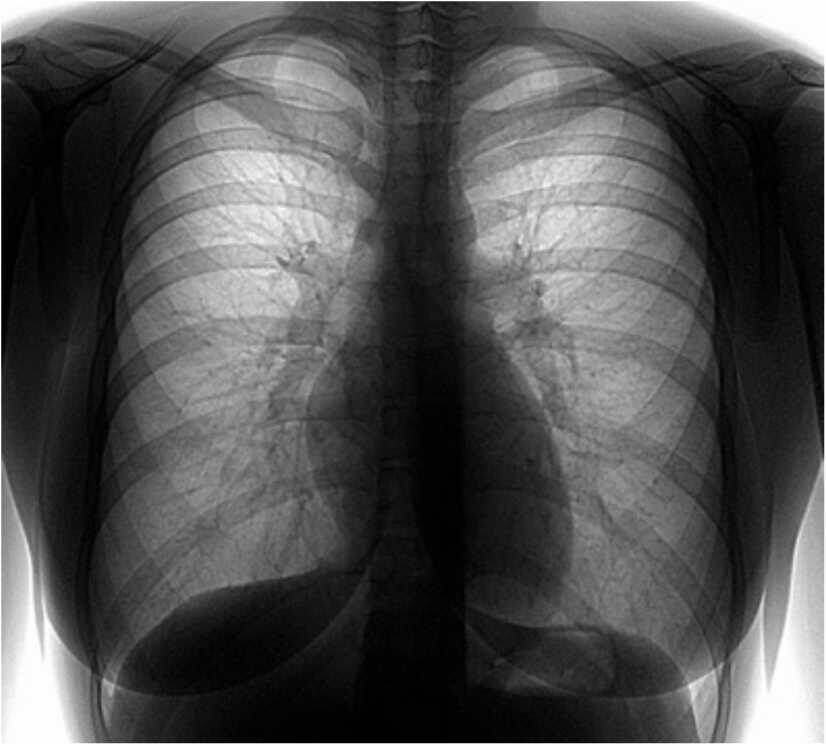

Но вот насколько она эффективна? Если в плане выявления туберкулеза ее выполнение оправдано, то для ранней диагностики онкологических заболеваний ее роль давно подвержена сомнениям. Развитые страны отказались от программ скрининга, использующих обычное рентгеновское исследование, так как не была доказана их эффективность. Это касается как «флюшки», так и рентгенографии легких. В рамках различных исследований не было выявлено снижения смертности при их использовании.

Наибольший интерес в плане выявления рака легкого на самых ранних стадиях вызывает использование низкодозной спиральной компьютерной томографии (НДКТ). В данной методике невысокая доза облучения - ниже в сравнении с рутинным исследованием. А результаты намного лучше по сравнению с классическим рентгеном – так уже отчетливо видны очаговые образования в легких с 2-3 мм. А по разным данным, достоверно на рентгенограмме и «флюшке» видны образования начиная с 10 мм, чаще от 15 мм. Определенные формы рака на флюорограмме вообще не видны до тех пор, пока не наступят катастрофические изменения.

Исследователи из-за океана опубликовали достаточно впечатляющие данные – согласно проведенному большому наблюдению с помощью НДКТ удалось снизить смертность от рака легких на 20%. В части исследований были указаны такие цифры – у 2% обследуемых был выявлен рак легкого, не менее чем у 80% из них на рентгенограмме не было никаких изменений. Стоит оговориться, что такие исследования проводятся обычно в группах риска (возраст старше 50-55 лет, курение).